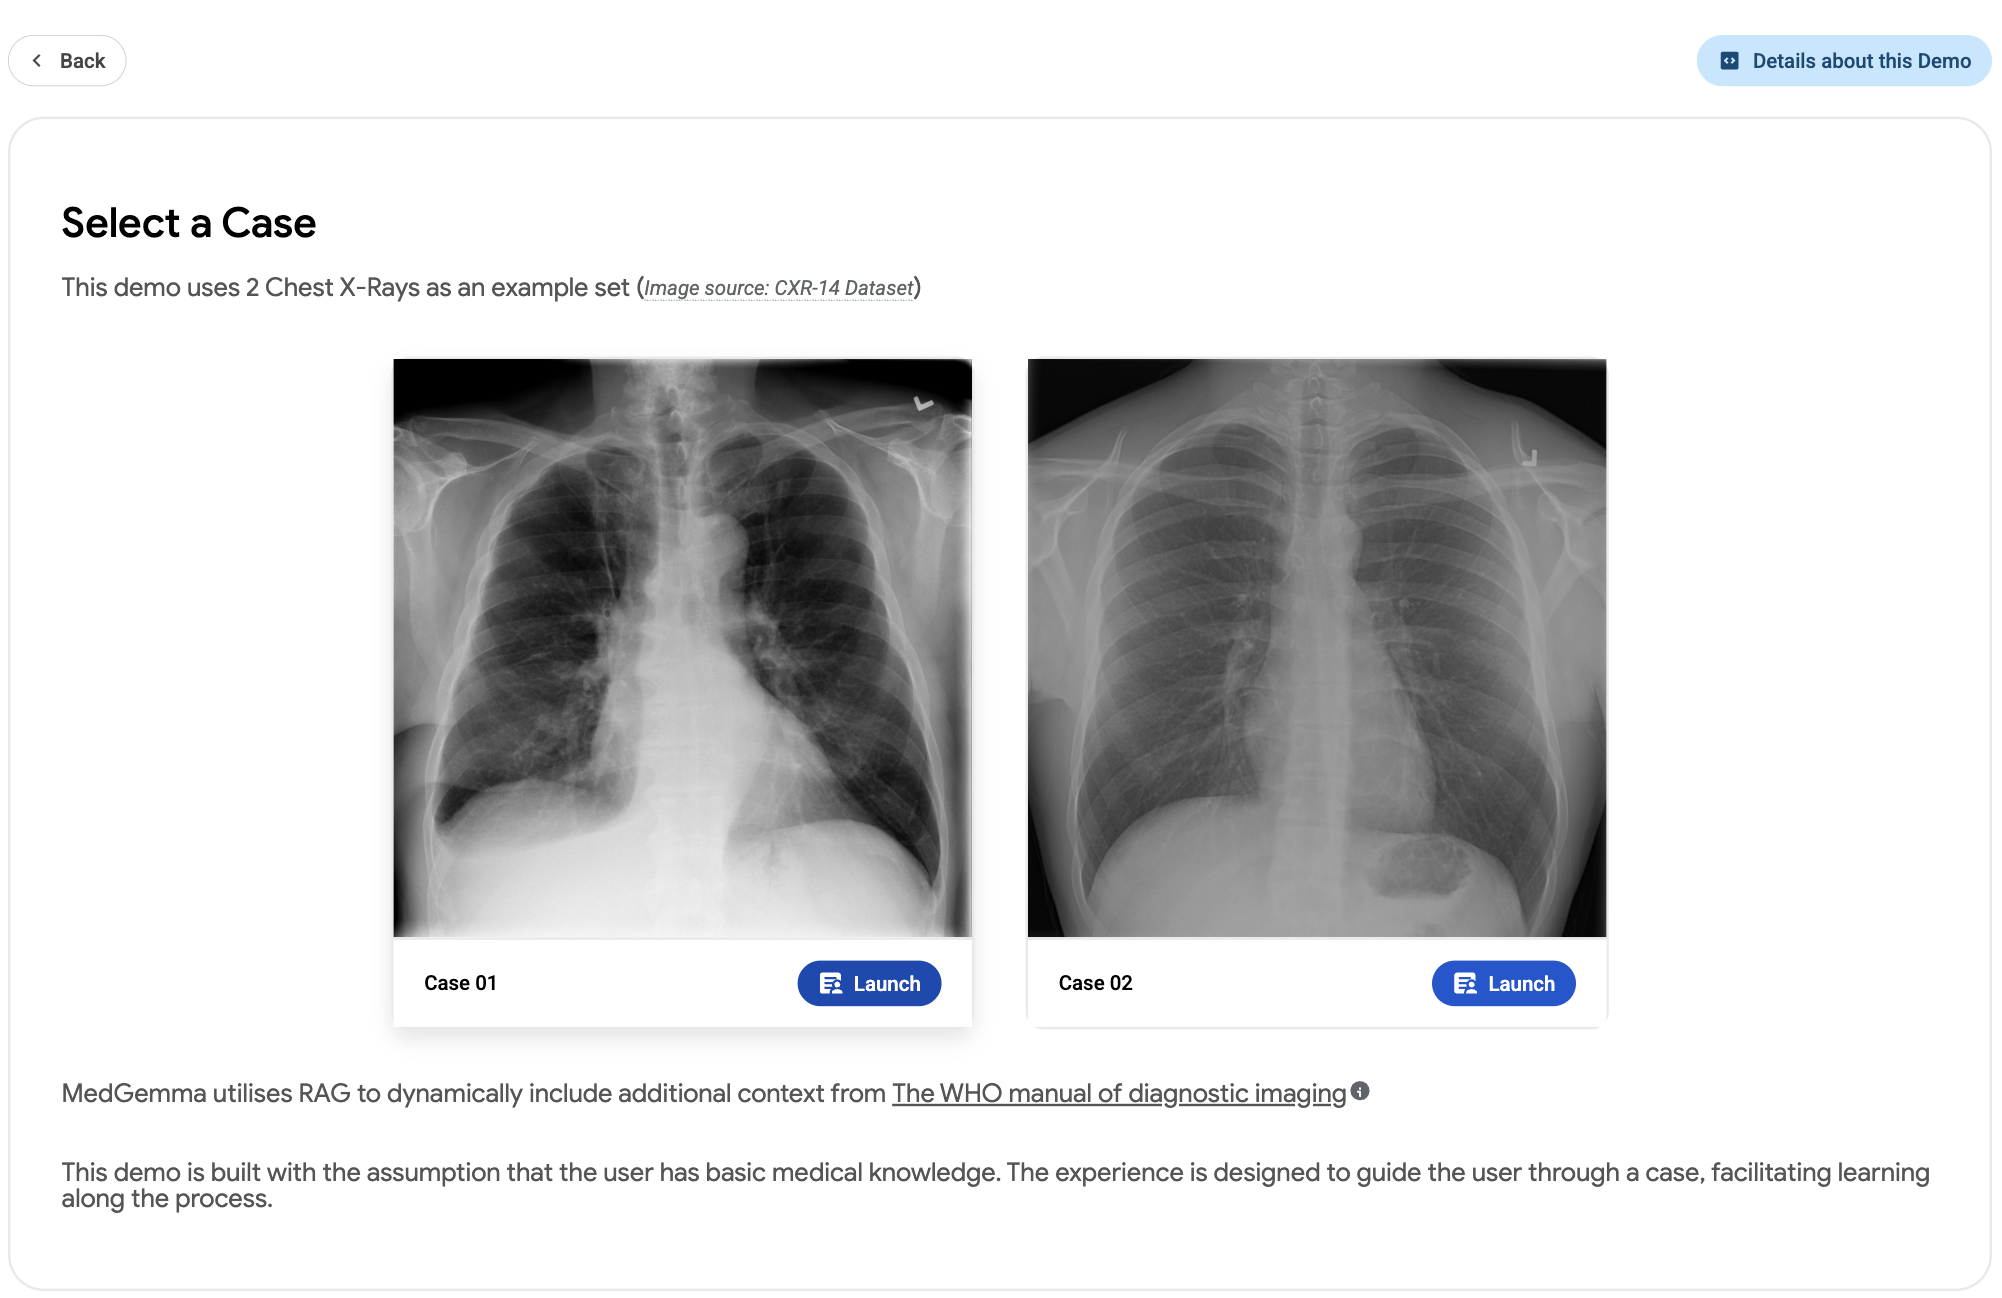

A demo showcasing a medical learning experience of CXR image